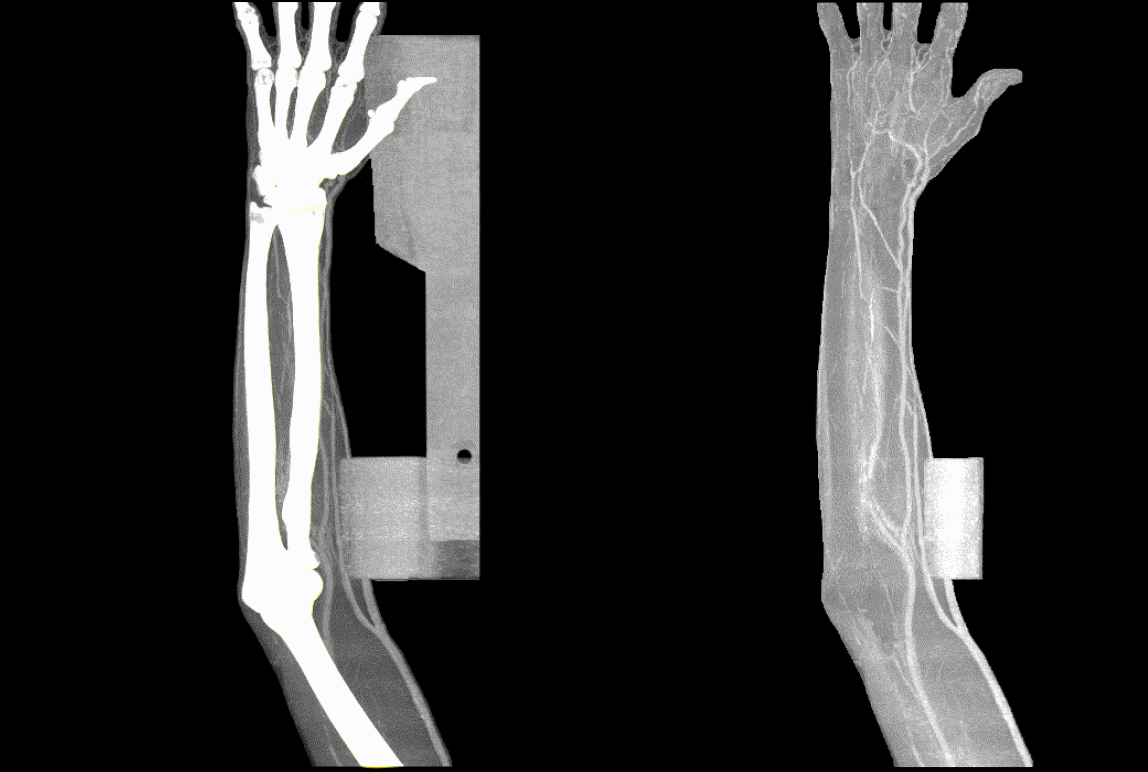

이렇게 학습된 인공지능 모델은 BAS보다 우월한 성능을 보일 뿐 아니라 놀랍게도 두경부 영상이 아닌 다른 부위의 영상에서도 어느정도 작동함을 확인할 수 있습니다.

ABS의 상지에의 응용

결론적으로 ABS는 조금의 학습 데이터만을 추가하여 미세 조정을 하게 되면 전신에서 잘 작동할 수 있을 것으로 기대됩니다.